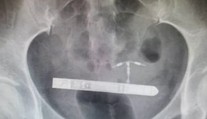

Pár si chcel spestriť romantické chvíle. Skončilo sa to bolestivými vibráciami v bruchu a operáciou Róbert Ďurkáč 28. 1. 2020